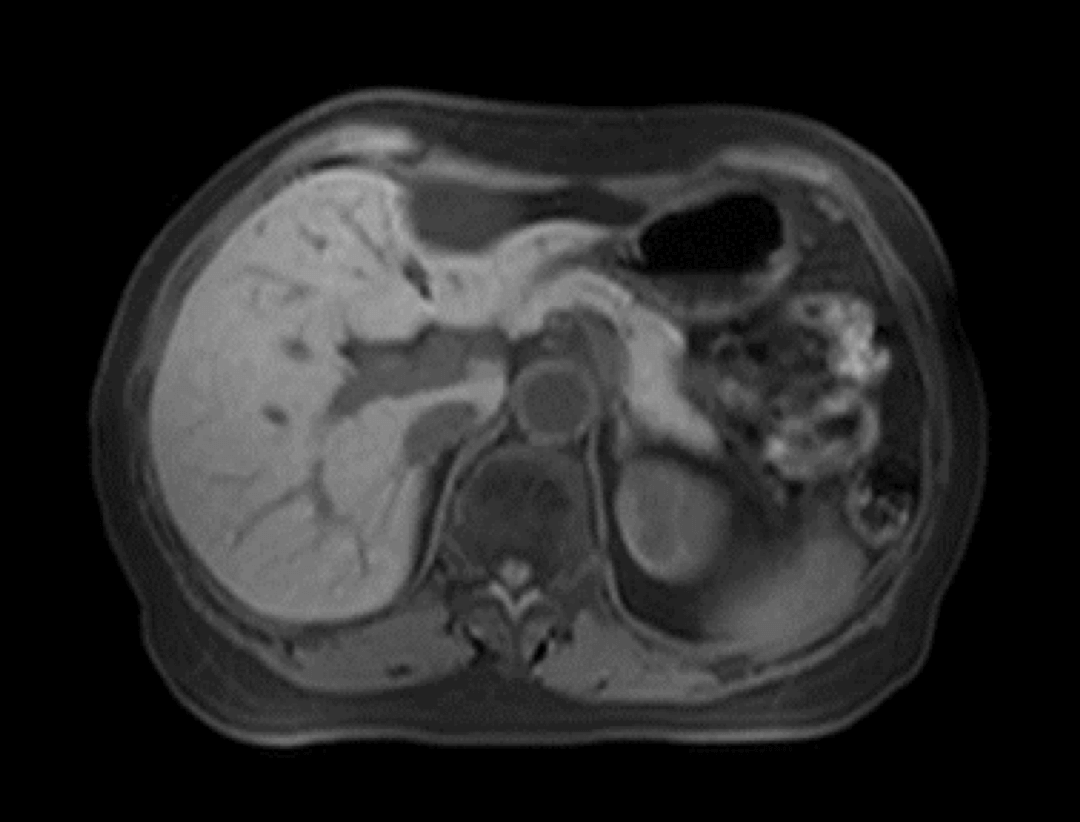

Tehnologia uCS® este utilizată în scanările dinamice abdominale cu substanță de contrast, permițând o accelerație de achiziție de până la 16× și captarea clară a modificărilor dinamice continue ale semnalelor tisulare.

Abdomen